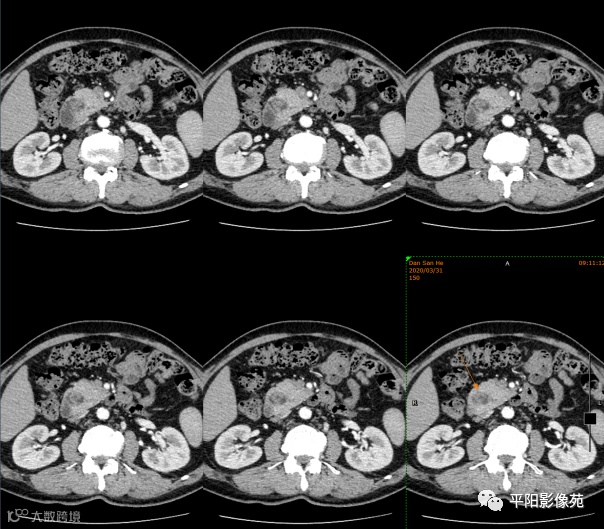

患者,男,49岁;

主诉:体检发现肝门淋巴结增大

影像表现:胰头环形包绕十二指肠降部

CT检查:主要征象为胰头部扩大,包绕十二指肠降段,导致十二指肠降段狭窄。增强扫描,胰腺组织明显强化,与十二指肠形成良好的对比。